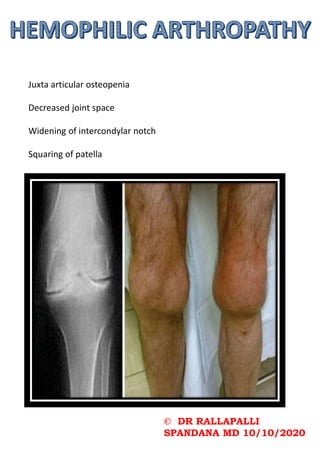

Juxta articular osteopenia

Decreased joint space

Widening of intercondylar notch

Squaring of patella